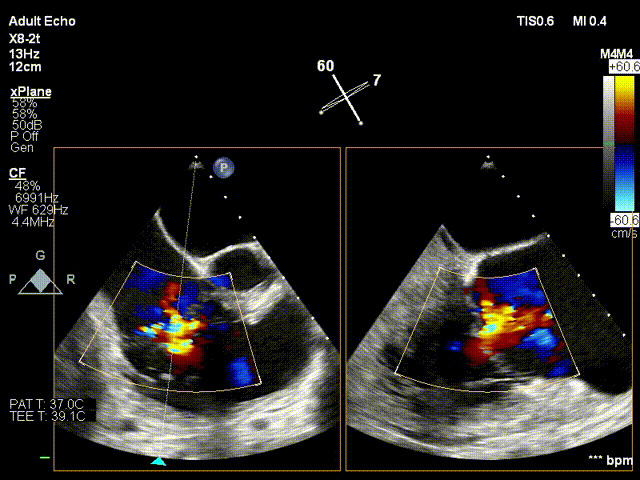

术前超声

术后超声